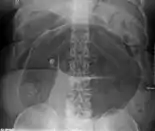

After taking a thorough history, the diagnosis of colonic volvulus is usually easily included in the differential diagnosis. Abdominal plain x-rays are commonly confirmatory for a volvulus, especially if a "bent inner tube" sign or a "coffee bean" sign are seen. These refer to the shape of the air-filled closed loop of colon which forms the volvulus. Should the diagnosis be in doubt, a barium enema may be used to demonstrate a "bird's beak" at the point where the segment of proximal bowel and distal bowel rotate to form the volvulus.

Volvulus with gangrene of the sigmoid